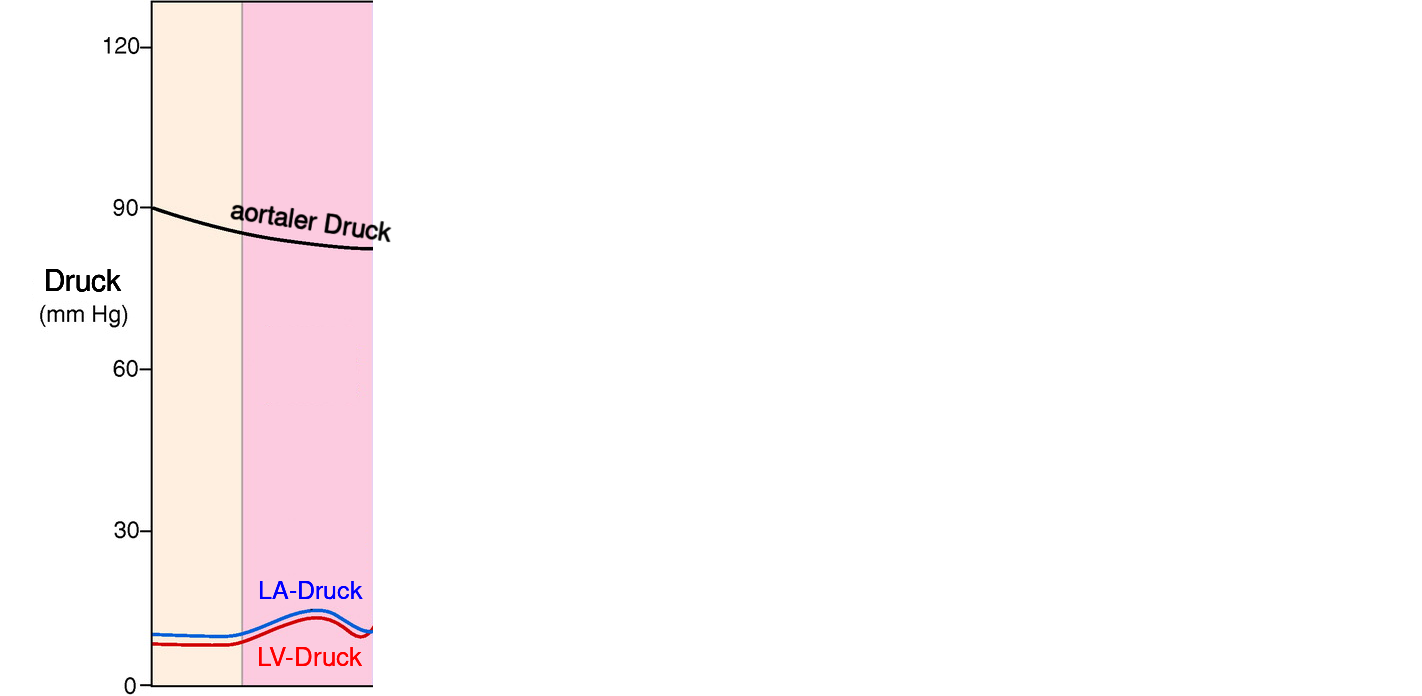

2 Phasen Herzaktion

- der ventrikulären Systole ist die atriale Systole vorgelagert

Vorhofkontraktion (atriale Systole)

- aktive linksventrikulären Füllung

- trägt zu 20 bis 30 Prozent zum gesamten linksventrikulären Füllungsvolumen bei

- erhöht normalerweise den diastolischen Druck hierdurch um weniger als 5 mmHg

die ventrikuläre Diastole (kardialer Input)

- entscheidend für die linksventrikuläre Füllung und damit der Herzfunktion

- für die Füllung muss der LV-Druck kleiner als der LA-Druck sein

- diastolischer LV-Druck wird bestimmt durch intraventrikuläres Blutvolumen, ventrikuläre Dehnbarkeit (Compliance) und durch den von Herzbeutel und rechter Herzkammer auf den linken Ventrikel ausgeübten externen Druck